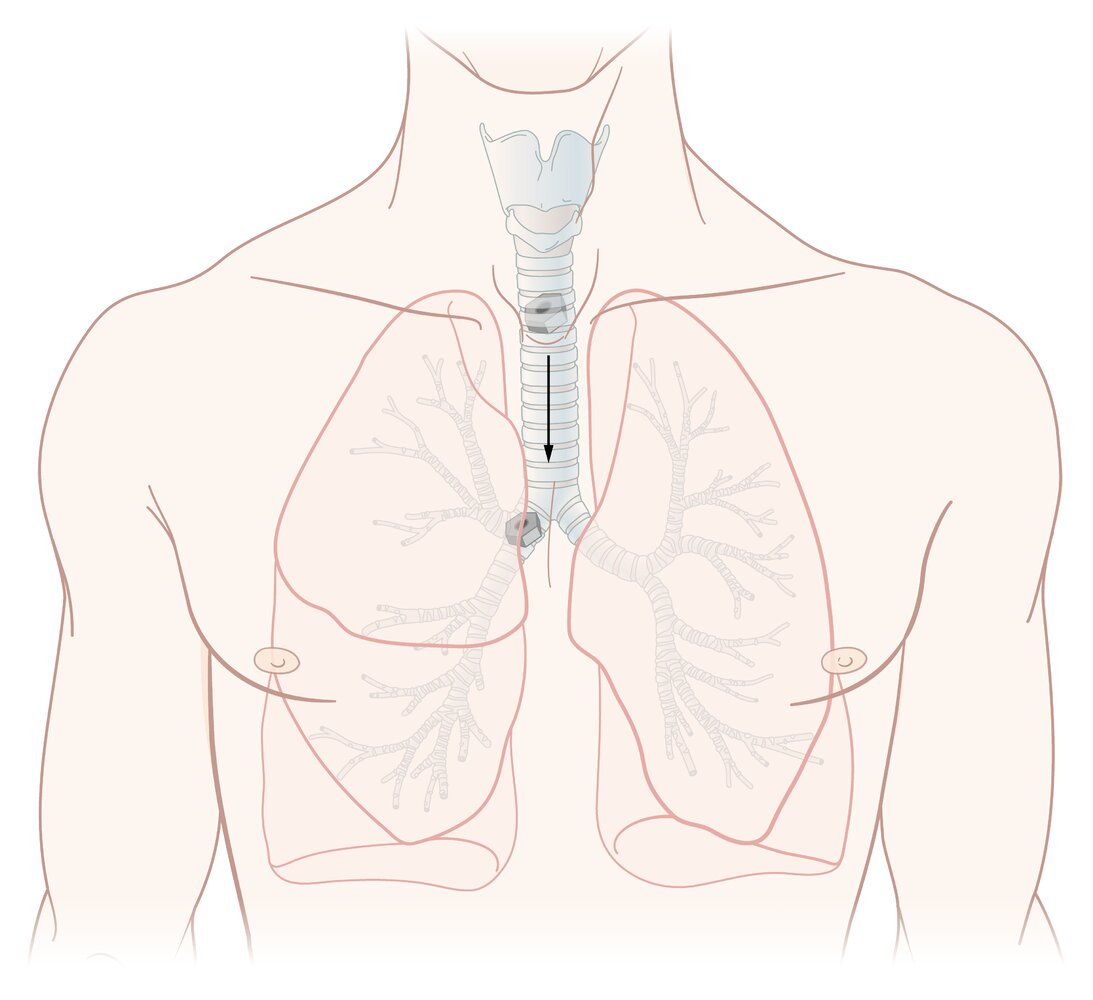

The respiratory system consists of a conducting zone (anatomic dead space; i.e., the airways of the mouth, nose, pharynx, larynx, trachea, bronchi, bronchioles, and terminal bronchioles) and a respiratory zone (lung parenchyma; i.e., respiratory bronchioles, alveolar ducts, alveolar sacs). The conducting zone is composed of nonrespiratory tissue and provides the passage for ventilation of the respiratory zone, where the O2 and CO2 exchange takes place. The respiratory system is furthermore divided into an upper tract (structures from the larynx upwards) and a lower tract (structures below the larynx). The entire respiratory tract down to the bronchioles is covered in ciliated epithelium, which provides immunologic protection by helping clear the airways of dust and microorganisms. Hyaline cartilage in the form of C-shaped rings (trachea) and plates (bronchi) provides structural protection and integrity. Gas exchange takes place in the alveoli of the lungs. The right lung consists of 3 lobes (upper, middle, lower), while the left lung consists of 2 lobes (upper, lower) and the lingula, a structure that is homologous to the middle lobe of the right lung. The left lung shares its space with the heart, which it accommodates in the cardiac notch. The development of the lungs begins in the embryonic period and continues until approximately 8 years of age.

• Trachea

• Formed by a series of cartilages (15–20), joined together by annular ligaments.

• Bifurcates at the level of T4 into the left and the right main bronchus (tracheal carina)

• Neighboring structures

• Posterior: esophagus, descending aorta

• Anterior: thyroid, ascending aorta, brachiocephalic trunk, superior vena cava